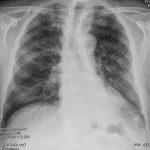

The appropriate position of radiology in COVID-19 diagnosis and treatment—current status and opinion from China

Progress and prospect on imaging diagnosis of COVID-19

COVID-19 and Italy: what next